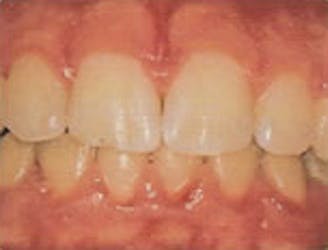

Gingivitis

- Gums bleed easily when you brush or when probed gently during an examination

- Gums are inflamed and sensitive to touch

- Possible bad breath and taste